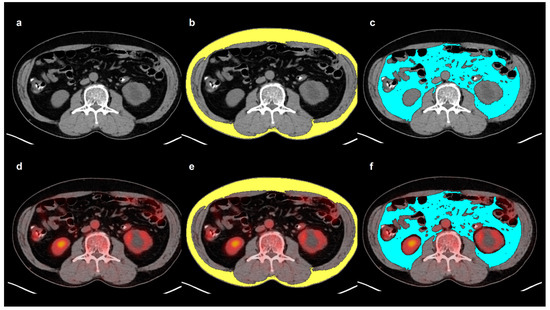

4.2. Adipose Tissue Imaging Parameter Measurements